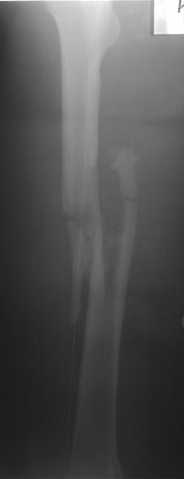

Уважаемые коллег, могу поделиться личным опытом лечения огнестрельных переломов в Республике Йемен. 230-250 больных за год. Пользуюсь класс, Густилло-Андерсон

Подход при 1,11, некоторых 111 А переломах "нетрадиционный -сберегательная хирургическая обработка, СОХРАНЕНИЕ всех костных отломков, первичный малоинвазивный остеосинтез LCP ( не нарушается периостальное и эндостальное кровоснабжение отломков, а при штифтовании нарушается эндост. кровоснабжение и риск медулярного остеомиелита), проточное дренирование, первичное закрытие ран, БЕЗ НАТЯЖЕНИЯ тканей или перв. отсроченные швы. При переломах 111В на первом этапе также СБЕРЕГАТЕЛЬНАЯ обработка с сохранением отломков и АВФ. Через две недели -МАЛОИНВАЗИВНЫЙ остеосинтез LCP

Я делал презентации на многих конференциях в России и за границей, также можно см журнал "ТРАВМ. ОРТОПЕДИЯ РОССИИ №2 2007 и 2 -2008

Привожу один из примеров

Р.S. Привожу клинический пример больного с огн. переломом бедра Густилло- Андерсон 111 А